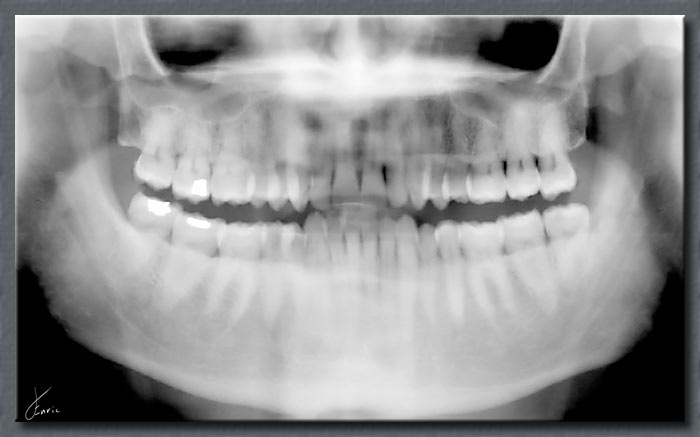

ORTOPANTOMOGRAFO DIGITALE

ALTISSIMA QUALITA’ DI IMMAGINE CON UNA BASSA DOSE

Sistema di imaging dentale di altà qualità con programmi di imaging comprendenti ortopanoramica, cefalometria ossea (telecranio AP/PA e LL) ed imaging a fascio conico (CONE BEAM).

Grazie a 2 campi visivi selezionabili e 4 impostazioni di risoluzione, combina accuratezza diagnostica, imaging rapido e BASSA DOSE DI ESPOSIZIONE.